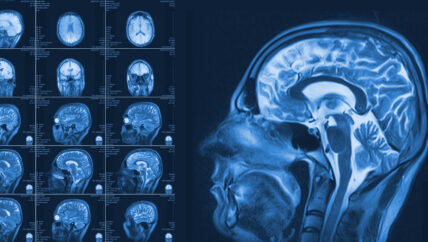

في غرفة الانتظار المخصصة داخل مشفى أورينت في إدلب، يجلس مرضى من مختلف الأعمار للحصول على صورة الرنين المغناطيسي لتشخيص أمراضهم، تطول فترة الانتظار وتقصر بحسب الحالة، إذ تصل […]